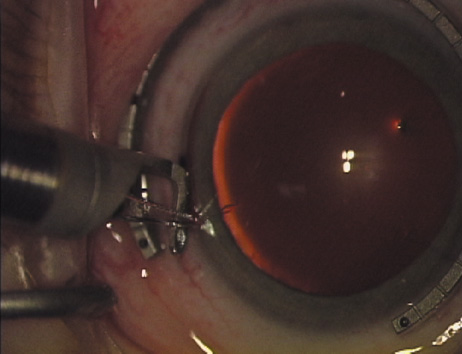

ways. Our preferred method makes use of a modified Fine-Thornton fixation

ring (Nichamin Fixation Ring and Gauge; Mastel Precision, Storz, Rhein

Medical). This instrument serves to fixate and position

the globe in order to optimize incision placement, as well as to delineate

the extent of arc to be incised. One visually extrapolates from

the limbus to marks on the surface of the ring. Each incremental mark

is 10 degrees apart, and bold hash marks (180 degrees) opposite

to each other serve to align and center the incision over the steep

meridian. This approach obviates the need to ink and physically mark

the cornea. If one desires, particularly when first gaining experience

with LRIs, a two-cut RK marker may be used to place ink marks upon the

cornea to show the exact extent of arc that is to be incised, in conjunction

with the fixation ring/gauge (Fig. 4). Alternatively, various press-on markers are available, such as

markers, rings, and blades for performing LRIs.  Fig. 4. The Nichamin Fixation Ring and Gauge serves to both fixate the globe and

delineate the extent of arc to be incised; a two-cut radial marker may

be used to mark the extent of arc to be incised, and the Mastel Nichamin

Force AK Diamond Blade with preset depth of 600 microns. Fig. 4. The Nichamin Fixation Ring and Gauge serves to both fixate the globe and

delineate the extent of arc to be incised; a two-cut radial marker may

be used to mark the extent of arc to be incised, and the Mastel Nichamin

Force AK Diamond Blade with preset depth of 600 microns.